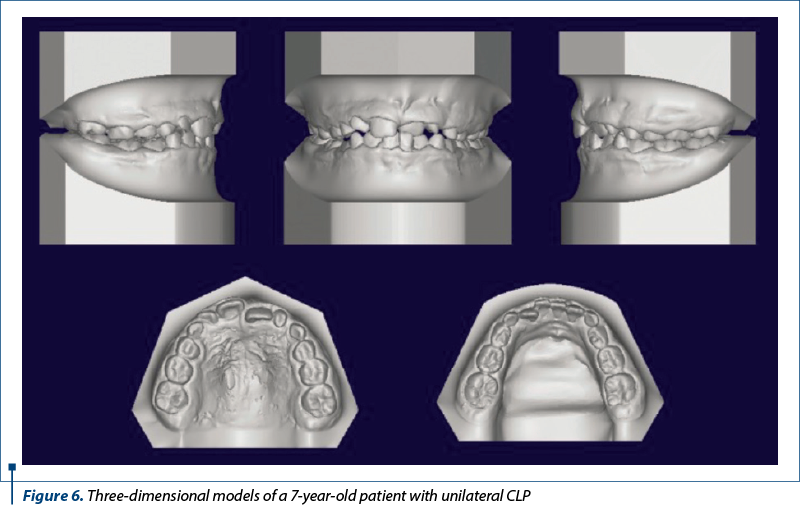

Impressions or dental models can be scanned with laser equipment, or intraoral scans can be performed to recreate 3D digitized dental models. 3D images have the advantage of allowing viewing by rotating on a 2D screen, which also facilitates accurate measurements. Physical models can be produced from the digital data by a computer-aided design/manufacturing (CAD/CAM) system (Figure 6), and can also be merged with the data obtained from the CBCT examination.

Three-dimensional imaging provides virtual models that can be manipulated to evaluate the effectiveness of various therapeutic methods. In complex cases, such as CL/P, this feature is especially valuable when the examination of the models is correlated with CBCT images that highlight the positioning of teeth likely to erupt in the cleft site. The orthodontist and surgeon can also use the merged images to determine the ideal graft volume needed for permanent teeth or possible osseointegrated implants.